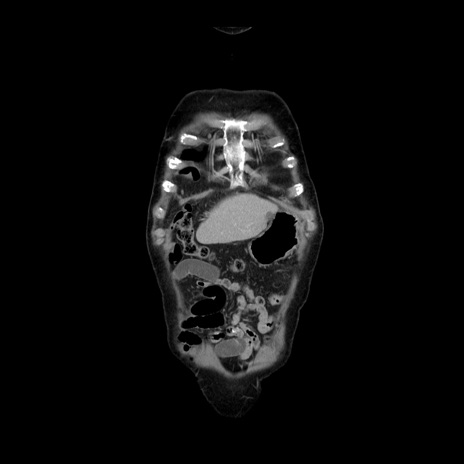

症例21(冠状断像)

【症例】70歳代男性

【主訴】腹痛

【現病歴】肝硬変・肝細胞癌にてかかりつけの方。約9時間前に食後より腹痛出現。症状が徐々に増悪し、嘔吐出現したため来院。

【既往歴】肝硬変、肝細胞癌(RFA、TACE後)

【身体所見】意識清明、表情苦悶様、BT 36℃、BP 129/78mmHg、P 88bpm、SpO2 97%(RA)、右上腹部から心窩部にかけて圧痛あり、反跳痛なし、筋性防御あり。

【データ】WBC 5800、CRP 0.16